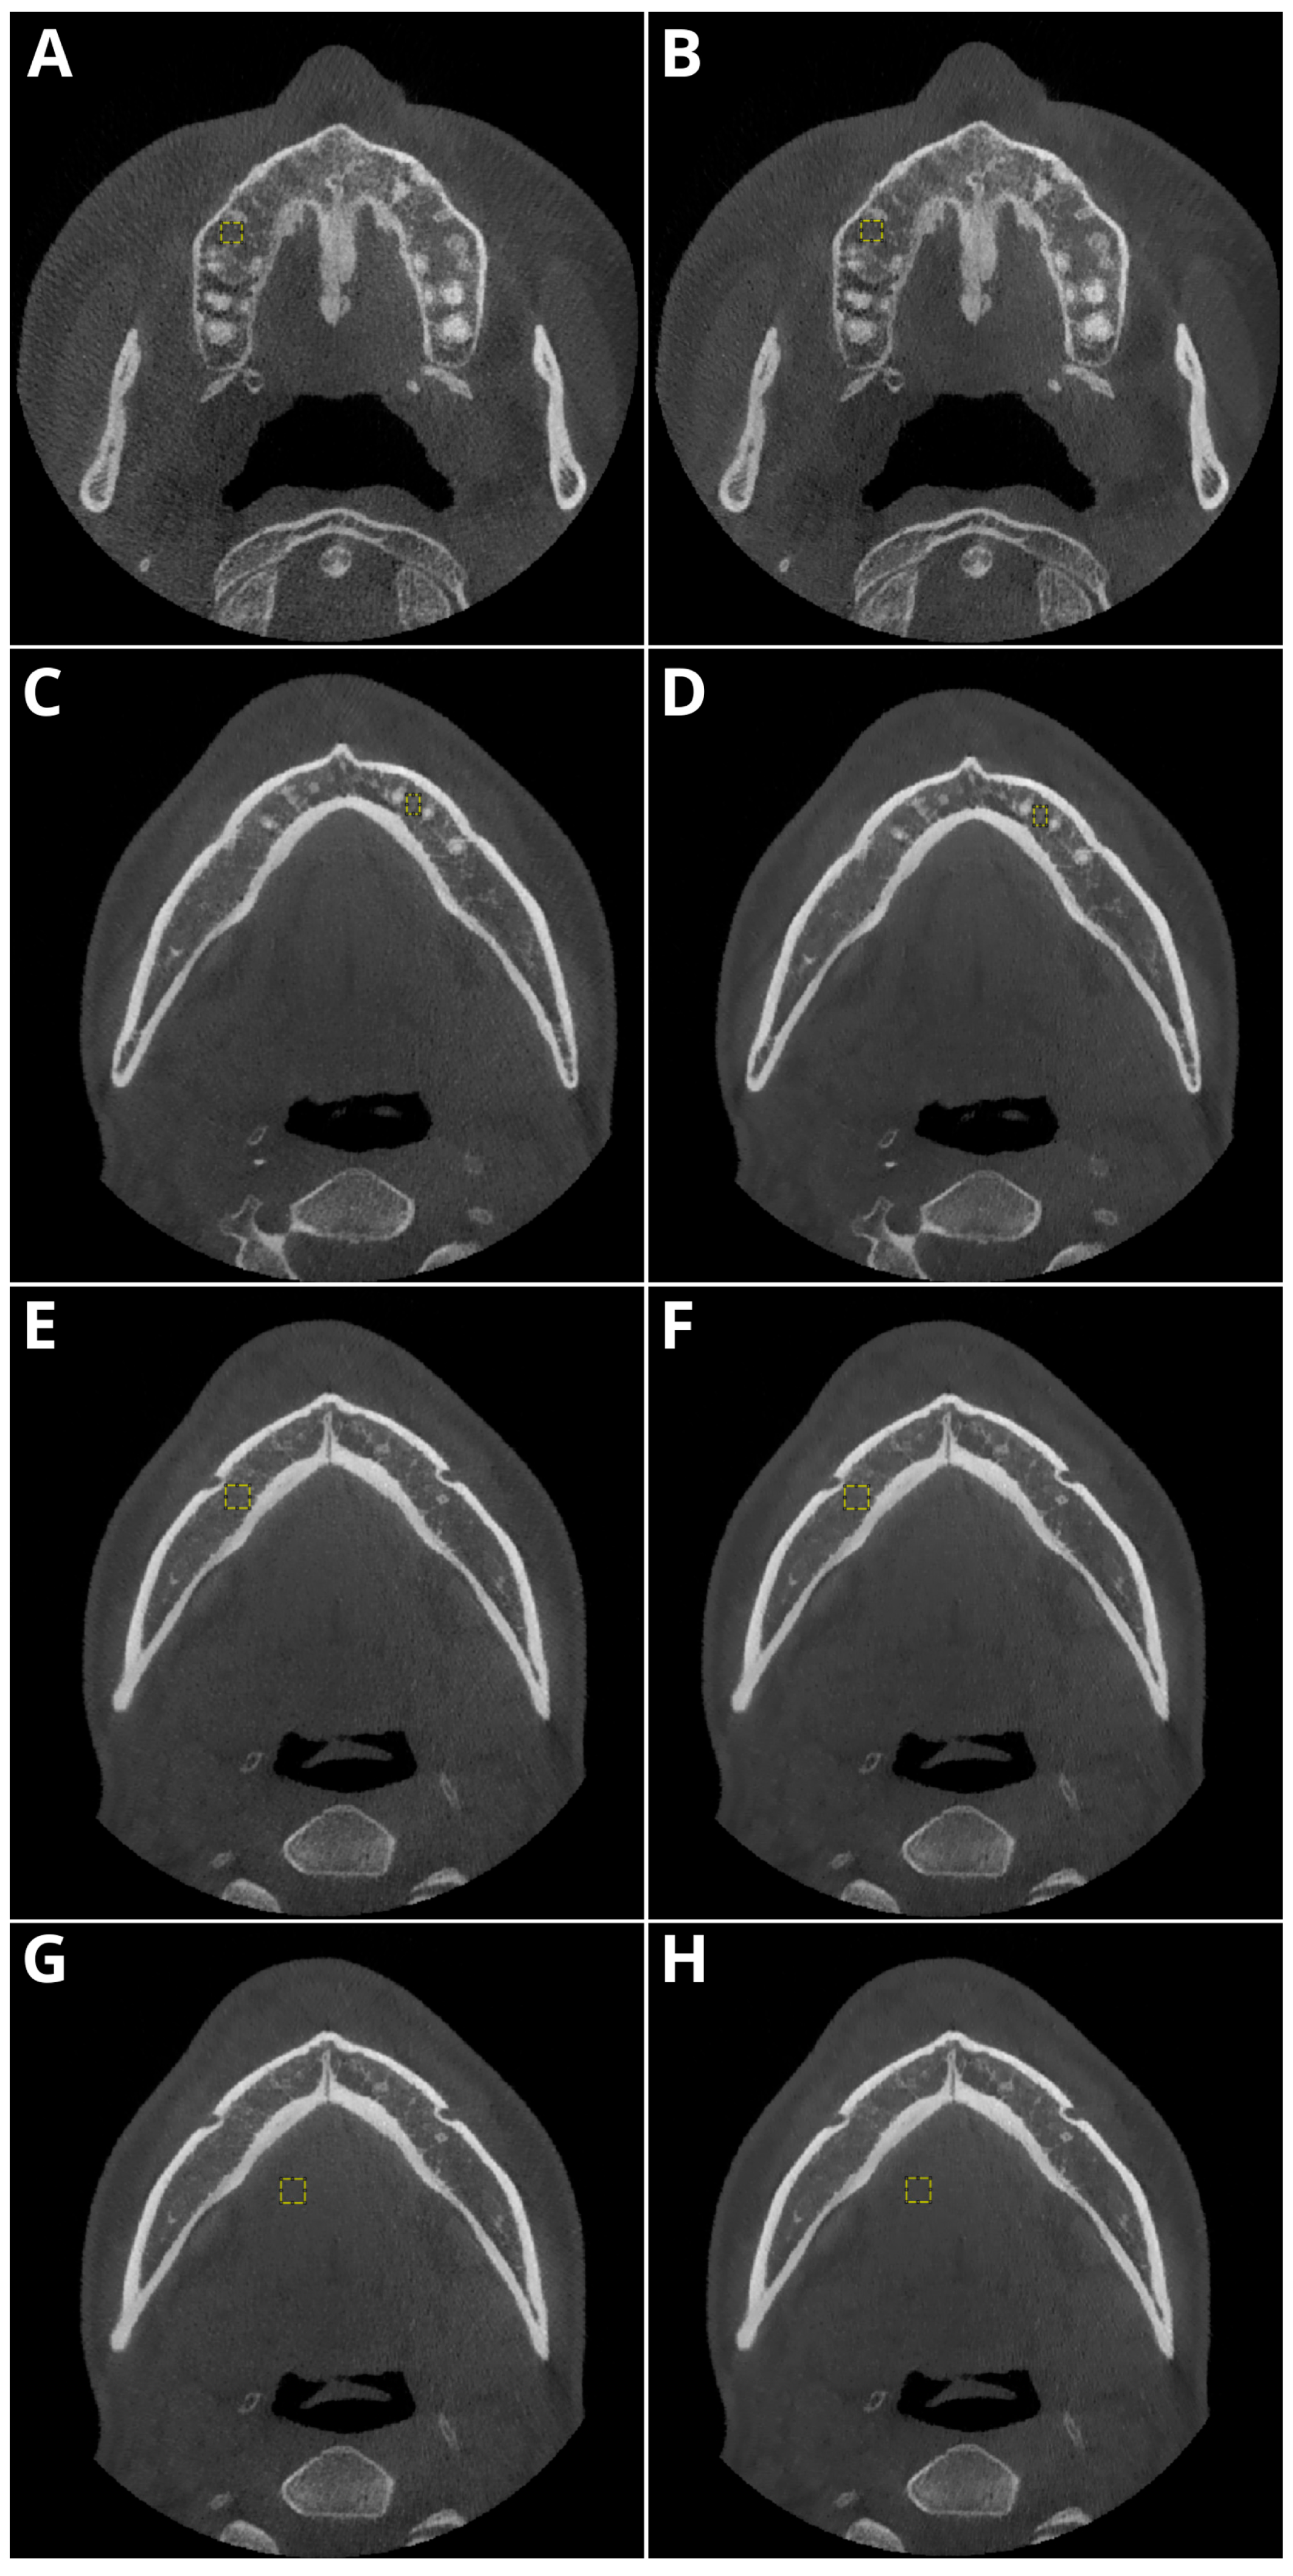

2.2. Image Acquisition and Postprocessing

2.3. Objective Image Quality

- Periapical region of tooth 15 within the maxillary bone,

- Periapical region of tooth 33 within the mandible,

- The spongious bone of the mandible in the mental foramen area,

- Muscles of the tongue.